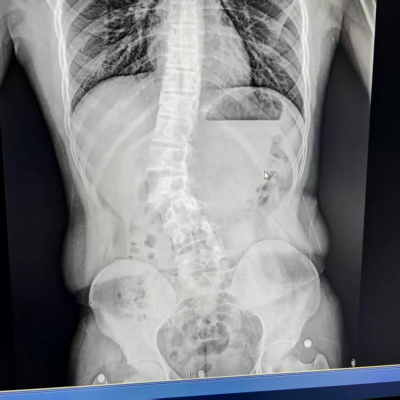

两年前,小林的母亲发现孩子双肩不等高、背部肌肉不对称,原以为是姿势不良所致,经立博体育

详细检查,确诊为青少年特发性脊柱侧弯(AIS)。影像显示,其脊柱以腰2为中心向右侧突出,范围从胸11延伸至腰4。

患者为青少年特发性脊柱侧弯,以腰2为中心向右侧突出,从胸11延伸至腰4